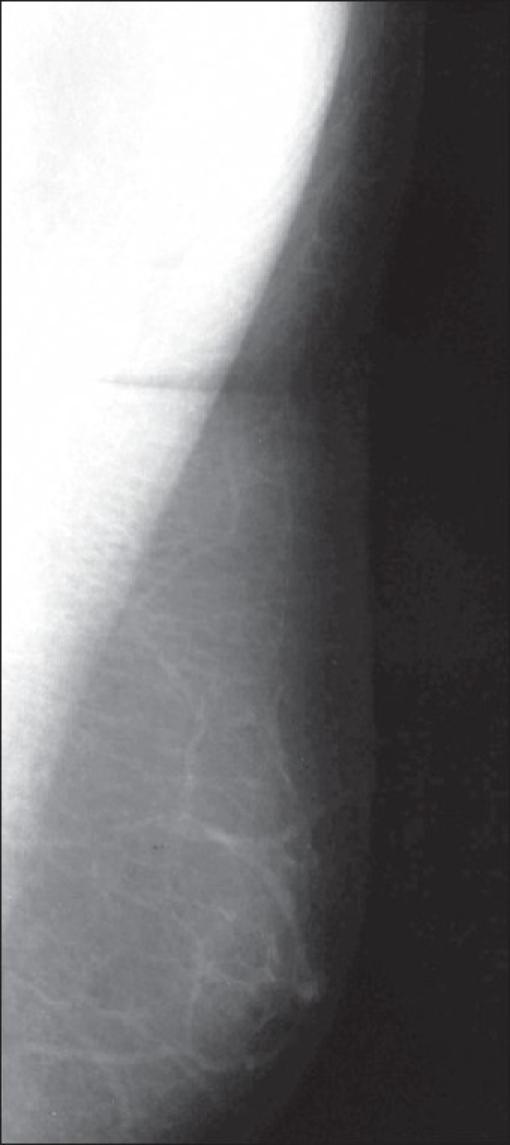

Pictorial essay: Mammography of the male breast.

Mammography is an imaging modality that is widely perceived to be of use only in women for the detection and diagnosis of breast pathologies. Here, we present a pictorial essay on the mammographic spectrum of male breast pathologies.

乳房X线摄影是一种成像方式,人们普遍认为它仅用于女性乳房疾病的检测和诊断。在此,我们展示一篇关于男性乳房疾病乳房X线摄影谱的图文文章。